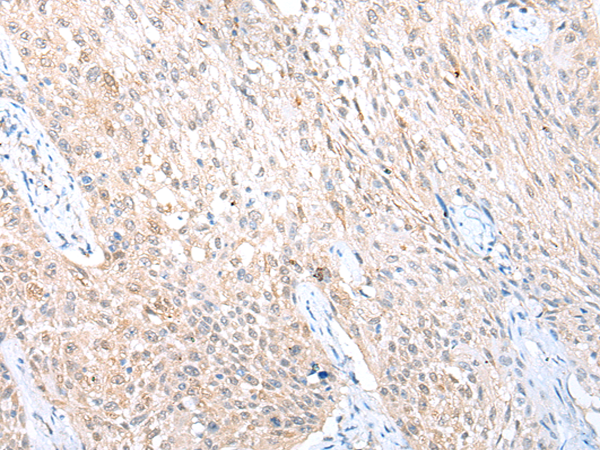

IHC positive control: |

Human liver cancer and human lung cancer |